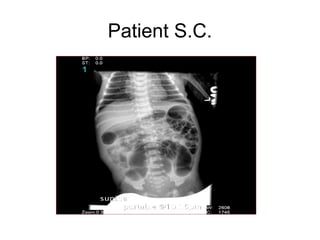

Patient S.C.

Barium Enema

• Less sensitive for detecting short lesions,

total colon aganglionosis, and disease of

the newborn

• Many newborns do NOT show definitive

transition zone

• Delayed evacuation of contrast

• #7 Narrow rectum, dilated sigmoid colon, normal appearing remaining large bowel.